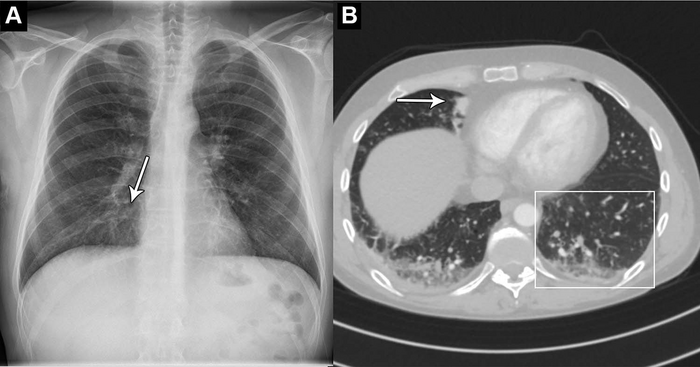

Chest X-rays are used to diagnose a wide variety of conditions to do with the heart and lungs. An abnormal chest X-ray can be an indication of a range of conditions, including cancer and chronic lung diseases.

Researchers used a commercially available AI tool to analyze the chest X-rays of 1,529 patients from four hospitals in the capital region of Denmark. Chest X-rays were included from emergency department patients, in-hospital patients and outpatients. The X-rays were classified by the AI tool as either “high-confidence normal” or “not high-confidence normal” as in normal and abnormal, respectively.

Of the 429 chest X-rays that were classified as normal, 120, or 28%, were also classified by the AI tool as normal. These X-rays, or 7.8 % of all the X-rays, could be potentially safely automated by an AI tool. The AI tool identified abnormal chest X-rays with a 99.1% of sensitivity.

“The most surprising finding was just how sensitive this AI tool was for all kinds of chest disease,” Dr. Plesner said. “In fact, we could not find a single chest X-ray in our database where the algorithm made a major mistake. Furthermore, the AI tool had a sensitivity overall better than the clinical board-certified radiologists.”